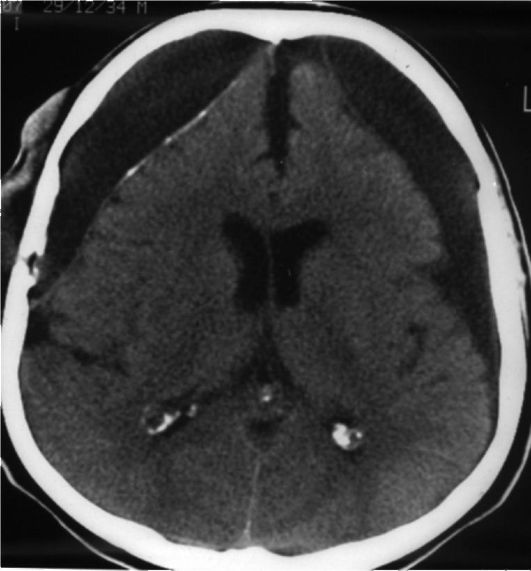

Медицинские аспекты и диагностика субдуральной гигромы мозга